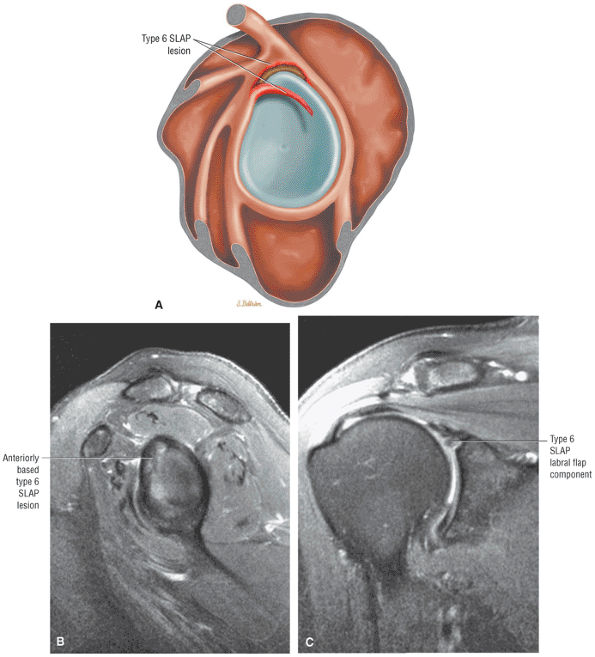

FIGURE 8.102 ● (A) The anterior undersurface of the acromion and the coracoacromial ligament form the coracoacromial arch. The subacromial subdeltoid bursa facilitates the passage of the rotator cuff and proximal humerus under the coracoacromial arch. (B) A superior axial image shows the anterior-to-posterior extent of the coracoacromial (CA) ligament perpendicular to the supraspinatus tendon. The fluid in the subacromial-subdeltoid bursa represents fluid between two serosal surfaces in contact with each other. One serosal surface is contributed by the undersurface of the coracoacromial arch and deltoid, and the other serosal surface is on the bursal side of the cuff.

|

![]() |

FIGURE 8.103 ● Pseudospur. The normal broad attachment of the coracoacromial ligament to the inferior surface of the acromion is shown on (A) T1-weighted coronal oblique and (B) sagittal oblique images. The low-signal-intensity acromial cortex (black arrows) and adjacent coracoacromial ligament and lateral slip of the deltoid attachment (white arrows) give the false impression of a small subacromial spur in the coronal plane. This pseudospur should not be misinterpreted as impingement; otherwise, unnecessary acromioplasties may be performed on patients with a normal coracoacromial ligament attachment and no associated acromial spurs.